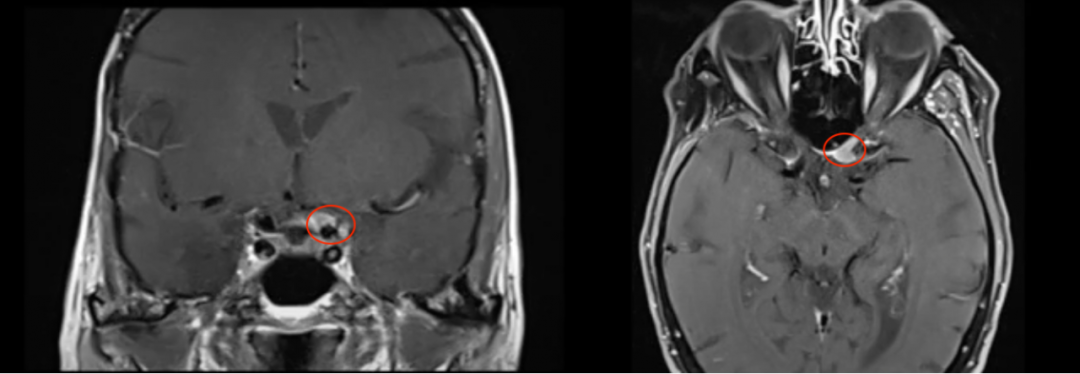

图片图5:术前术后MRI影像对比,肿瘤全切除

术后情况:Chloe术后核磁显示肿瘤完全切除,术中无功能神经损伤,无脑脊液渗漏等手术并发症,视神经保留完好,术后患侧视力也得到好转。